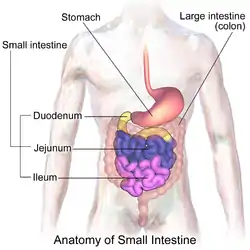

Image of the gastrointestinal tract, with the duodenum highlighted. | |

Diagram of the human duodenum with major parts labelled | |

The duodenum (/duːˈwɑːdɪnəm/ doo-WAH-dih-nəm, /duːoʊˈdiːnəm/ doo-oh-DEE-nəm) is the first section of the small intestine[2] in most higher vertebrates, including mammals, reptiles, and birds. In mammals it may be the principal site for iron absorption. The duodenum precedes the jejunum and ileum and is the shortest part of the small intestine.

In humans, the duodenum is a hollow jointed tube about 25–38 centimetres (10–15 inches) long connecting the stomach to the middle part of the small intestine.[3][4] It begins with the duodenal bulb and ends at the suspensory muscle of duodenum.[5] Duodenum can be divided into four parts: the first (superior), the second (descending), the third (transverse) and the fourth (ascending) parts.[4]

The duodenum is the first section of the small intestine in most higher vertebrates, including mammals, reptiles, and birds. In fish, the divisions of the small intestine are not as clear, and the terms anterior intestine or proximal intestine may be used instead of duodenum.[6] In mammals the duodenum may be the principal site for iron absorption.[7]

In humans, the duodenum is a C-shaped hollow jointed tube, 25–38 centimetres (10–15 inches) in length, lying adjacent to the stomach (and connecting it to the small intestine). It is divided anatomically into four sections. The first part lies within the peritoneum but its other parts are retroperitoneal.[8]: 273